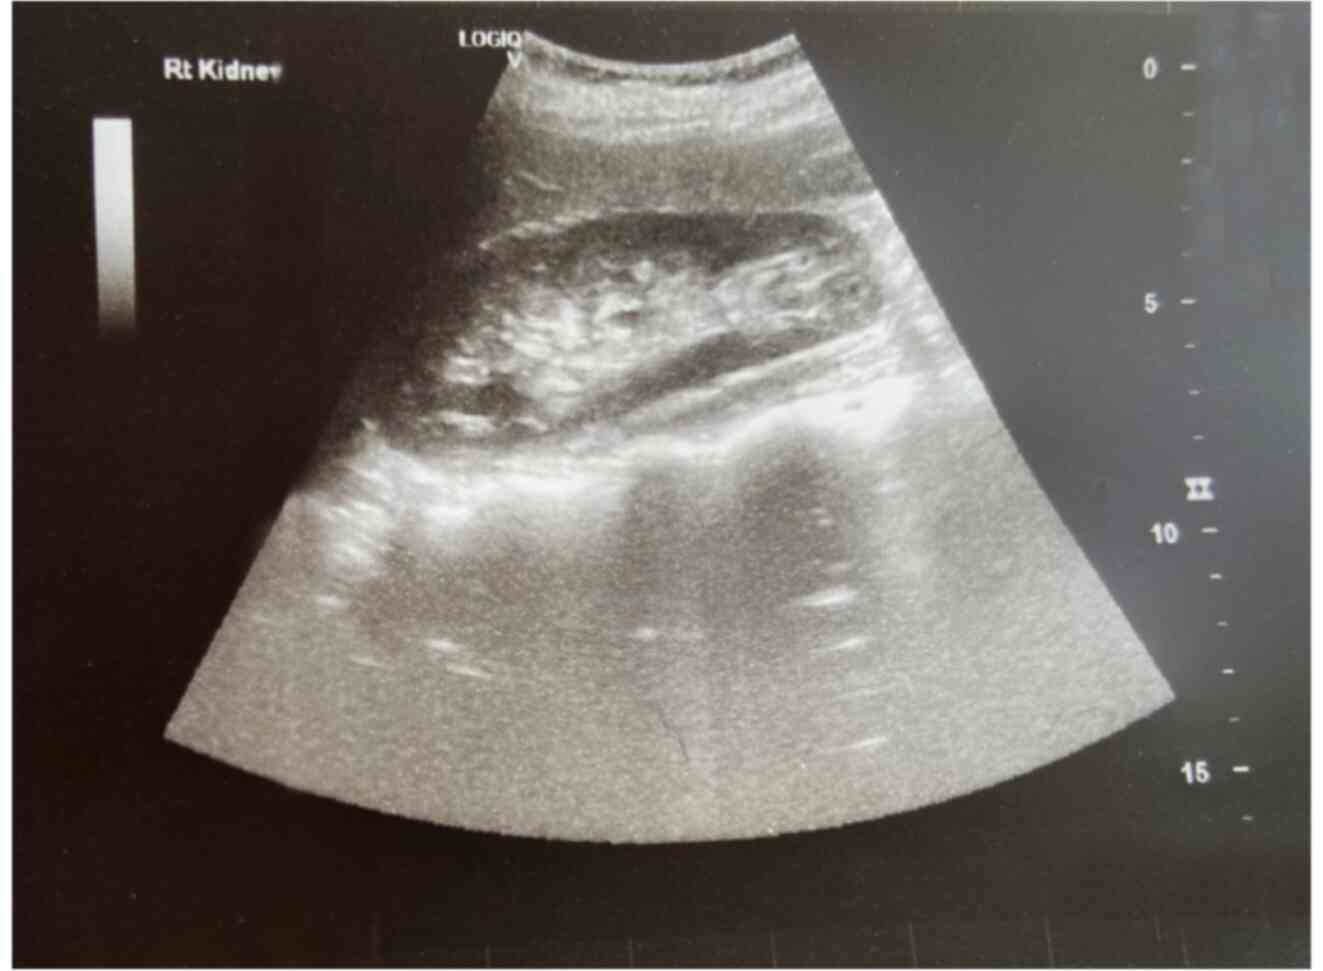

Large bladder flap haematoma following a caesarean section associated with right hydroureteronephrosis: A case report and a mini‑review of the literature

Post‑caesarean section bladder flap haematoma is a rare postpartum complication. There are currently no specific treatment protocols, at least to the best of our knowledge. In general, the failure of conservative treatment with antibiotics requires the re‑operation and surgical drainage of the haematoma. The present study describes the case of a primiparous pregnant woman who, at 40 weeks of pregnancy, delivered by caesarean section. On the 3rd post‑operative day, the puerperant, haemodynamically stable, developed febrile infection. During the evaluation, the presence of bladder flap haematoma associated with moderate right hydroureteronephrosis was found. The failure of conservative management led to the decision to perform a re‑laparotomy 1 week later. During the surgery, a large bladder flap haematoma was found with a retroperitoneal extension into the right parametrium. The surgical drainage of the haematoma and thorough haemostasis in the area of the vesicouterine pouch was performed. The patient was discharged from the clinic on the 5th post‑operative day following the re‑operation. After 2 weeks, an ultrasound revealed the complete repair of the lesions in the vesicouterine pouch and the right kidney. In the present study, a brief review of literature is also provided regarding the diagnostic and therapeutic management of patients with post‑caesarean section bladder flap hematoma.

Figure 1